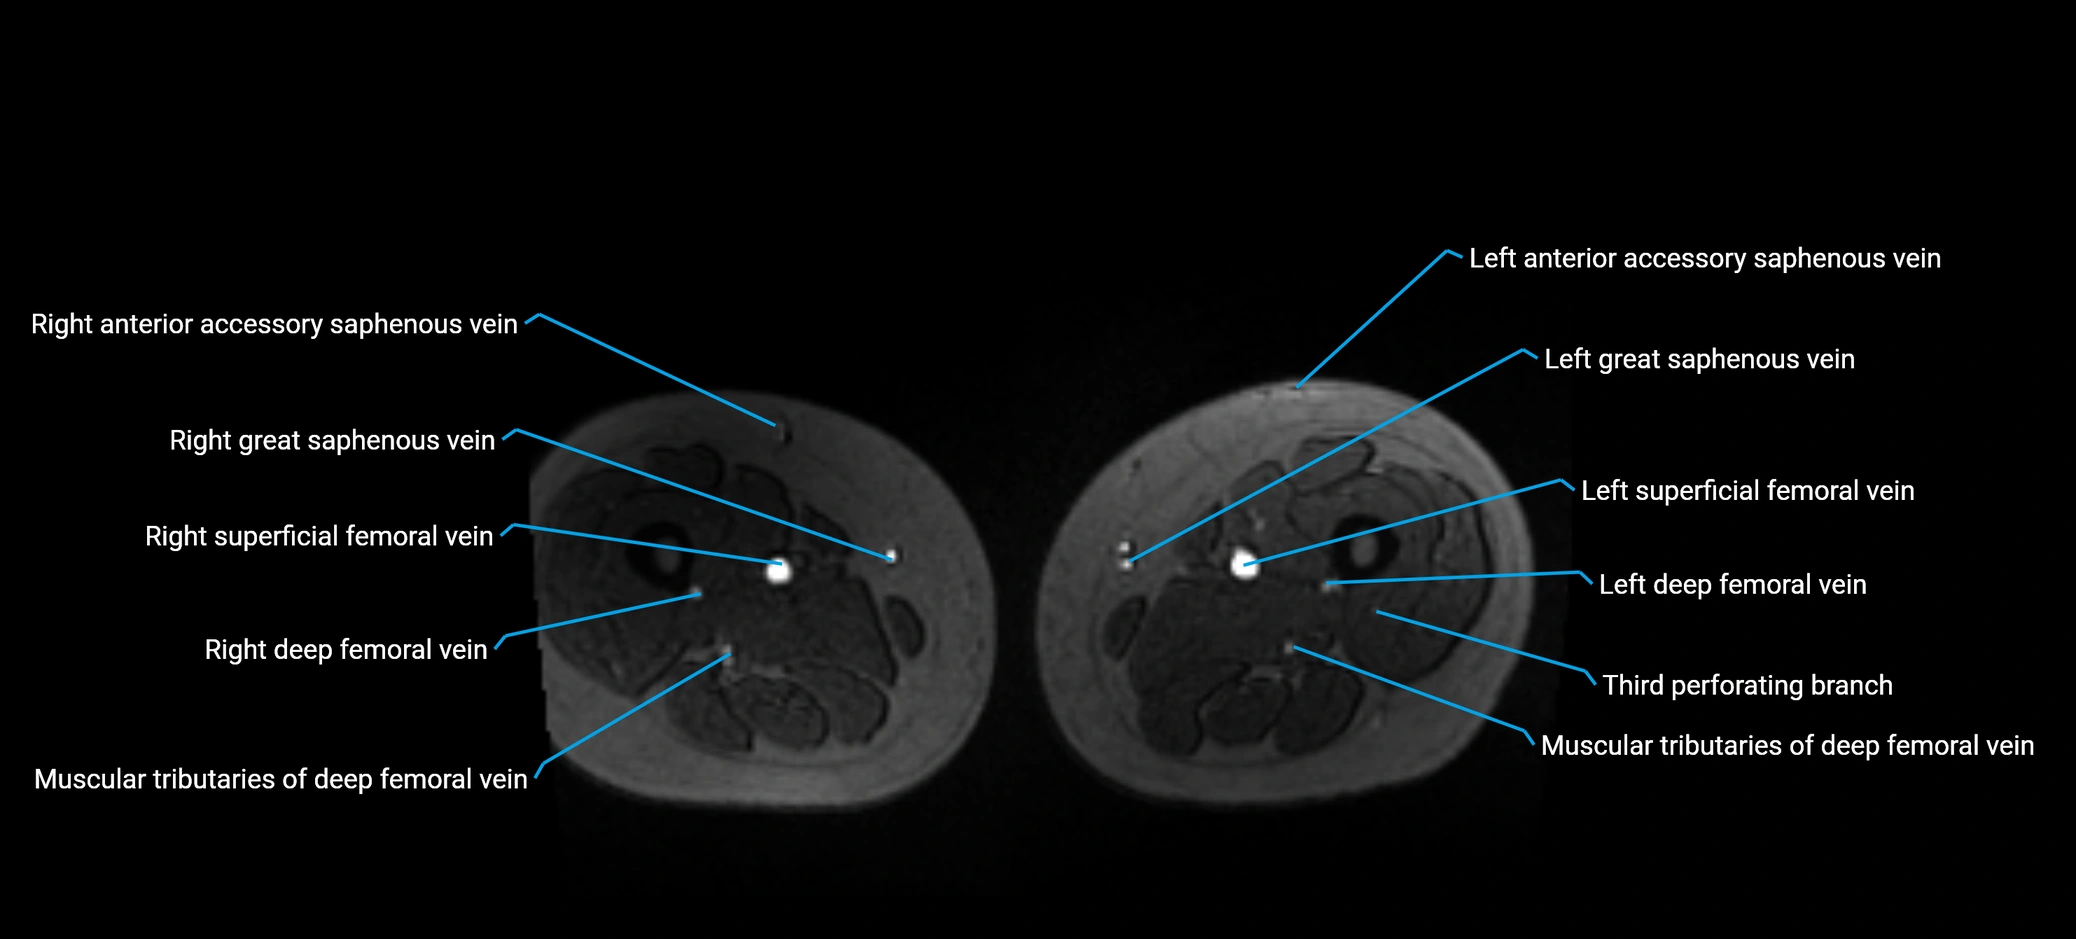

MRI image

image